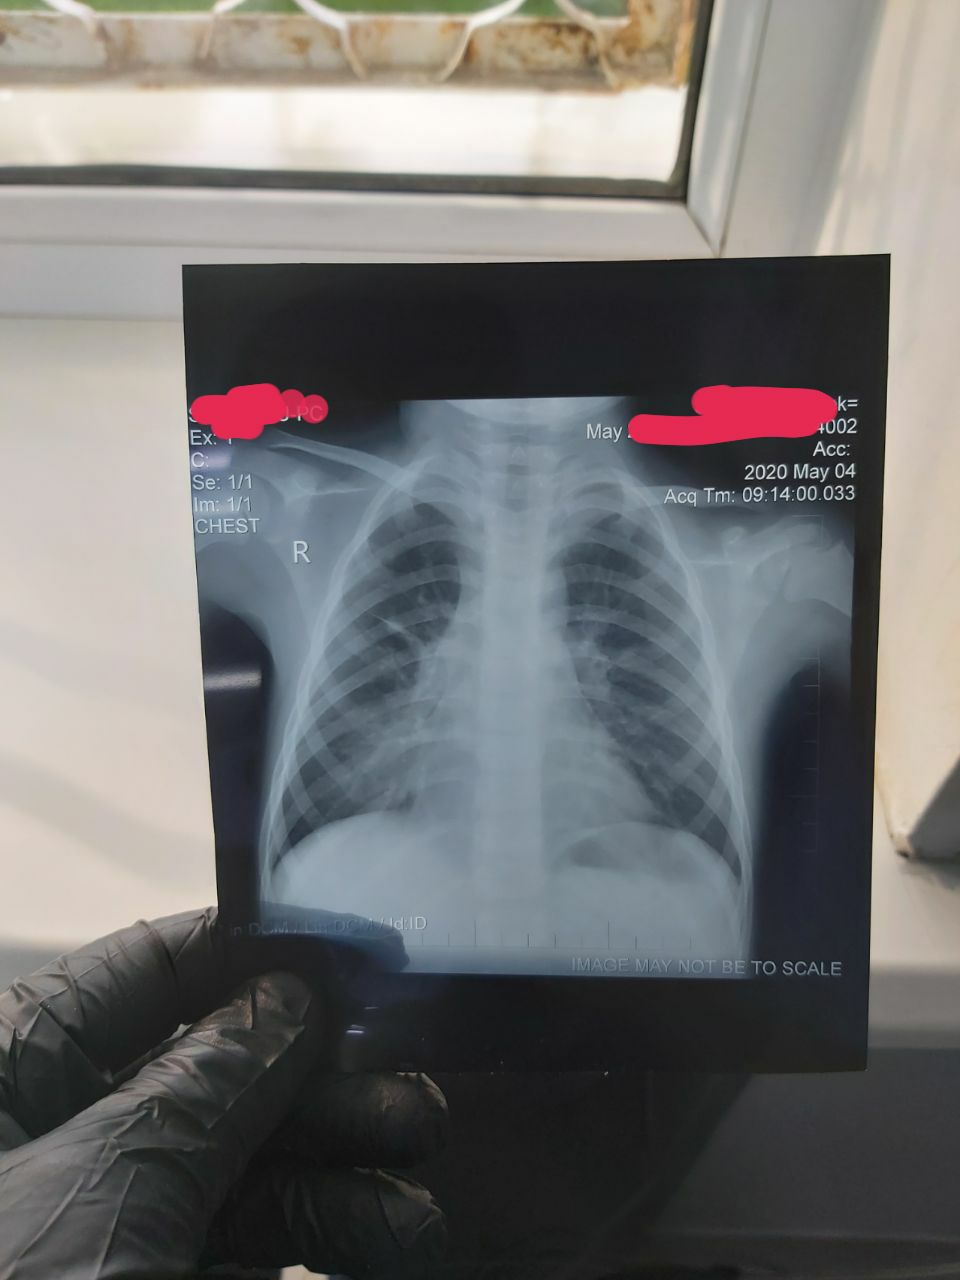

6 лет

Жалоба кашел, температура 38-38.5

Правосторонняя пневмония

23.04.2020

04.05.2020

Поавостронняя сегментарная пневмония...

Пневмония правосторонняя похоже